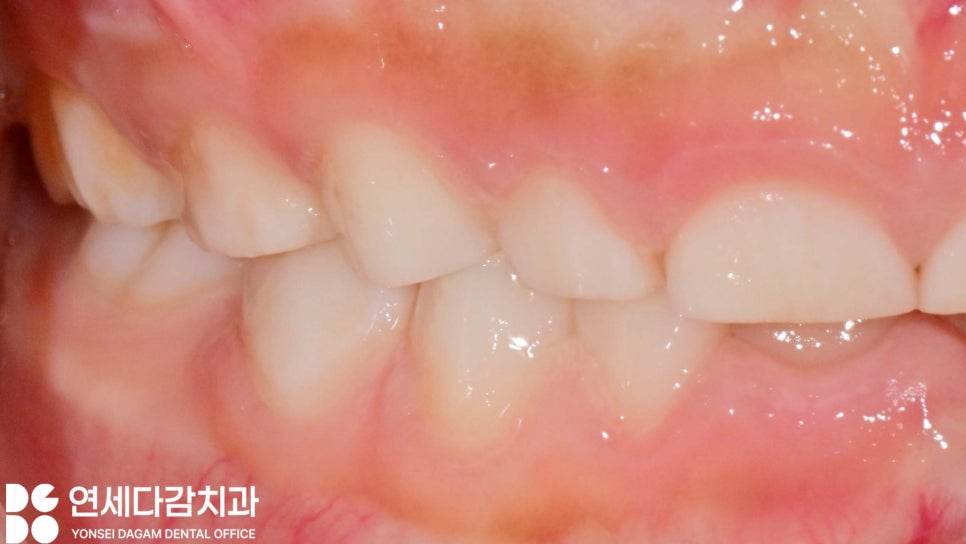

간혹 아이가 이를 심하게 갈아서

치아가 닳아 짧아진 형태가

되기도 합니다.

생각보다 많이 짧아진 모습에 당황스럽고

혹시 크게 문제가 되는 건 아닌가..

걱정하실 때가 많은데,

막상 아이는 대부분 통증도 크게

못 느끼며 특별한 치료가

필요 없는 경우가 많습니다.

오금역 치과 에서 보여드린 것처럼

앞서 설명드린 원인들로

치아 크기의 절반이 되도록 이를 갈아도

문제로 삼지 않을 때가 많습니다.